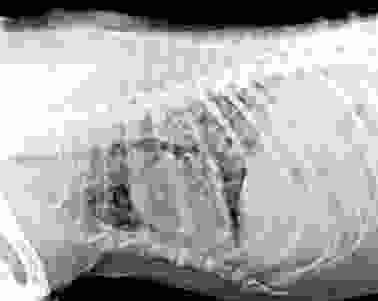

如何診斷狗腫瘤轉移肺部?

診斷需要多管齊下,獸醫通常會做以下檢查:

| X光檢查 | 查看肺部有無陰影或結節 | 最基礎的篩查,但小腫瘤可能漏掉 |

獸醫可能會建議從X光開始,如果發現異常,再進階到CT。活檢是黃金標準,但有些家長擔心風險,其實現在技術很安全。台灣大學獸醫專業學院有篇研究指出,早期診斷能顯著提升治療成功率。

我有個朋友帶狗狗做檢查時,獸醫用了X光發現肺部有多個小點,後來CT確認是轉移。他們慶幸沒拖延,否則後果更嚴重。